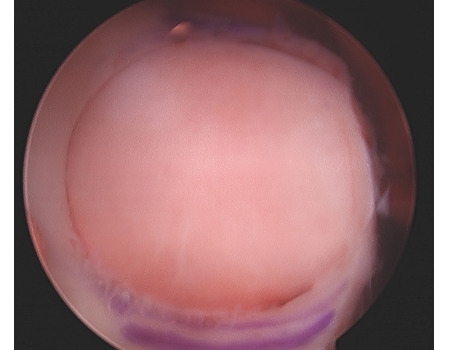

Arthroscopic View of Large Trochlear Chondral Lesion

Arthroscopic View of Implanted OATs